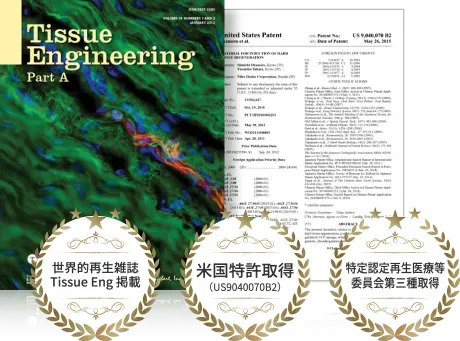

世界にみとめられた プルージュのPRP

プルージュ リジェン クリニック理事長は、PRPがまだ一般的に知られていない2010年よりPRPを使った再生治療の研究を重ねてきました。

その研究が、2012年に組織再生工学の国際的ジャーナル「Tissue Engineering」で論文が紹介されました。

さらに本法はアメリカで特許を取得しております。

そういった海外での評価も我々が治療の効果に自信をもっておすすめできる理由です。